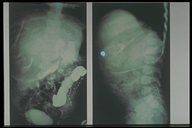

A plain X-ray of a child with intraabdominal mass" fetus in fetu"